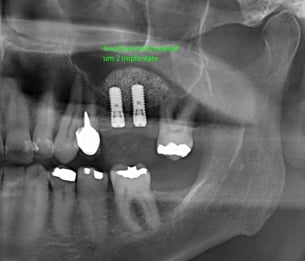

Implantologie

Senioren -"MINI" Implantate